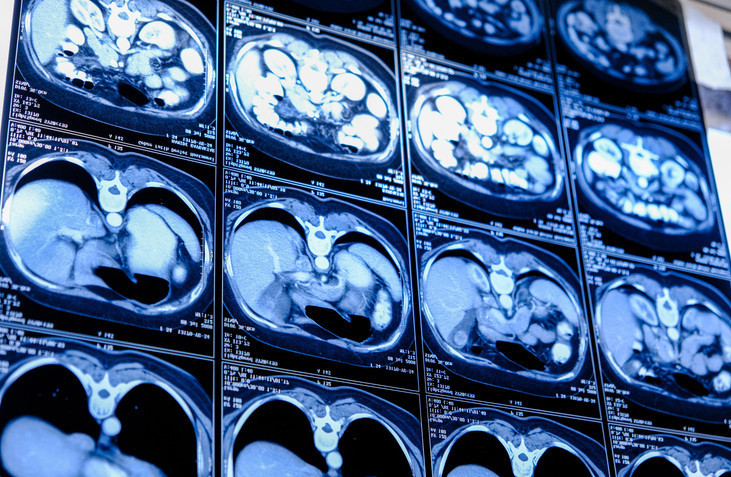

Zatürre, akciğerlerdeki küçük hava keseciklerini etkileyen bir göğüs enfeksiyonu olarak tanımlanıyor. Hastalar nefes almakta zorlanabilir, bazı durumlarda kan öksürebilir veya solunum cihazına bağlı olarak yaşam mücadelesi verebilirler. İngiltere ve Galler’de 2024 yılında 23.061 kişinin yaşamını yitirdiği istatistiklerde, zatürre ve grip birlikte ölüme neden olan en önemli faktörler arasında gösteriliyor.

Zatürre belirtileri arasında hırıltı, öksürük ve akciğerlere yeterli hava girememe bulunur. Bu durum, hayati organların temel işlevlerini yerine getirmesini zorlaştırır. Zatürreye bağlı en ciddi komplikasyon ise sepsistir; kanın enfekte olup toksik hale gelmesi, çoklu organ yetmezliğine ve ölüme yol açabilir.